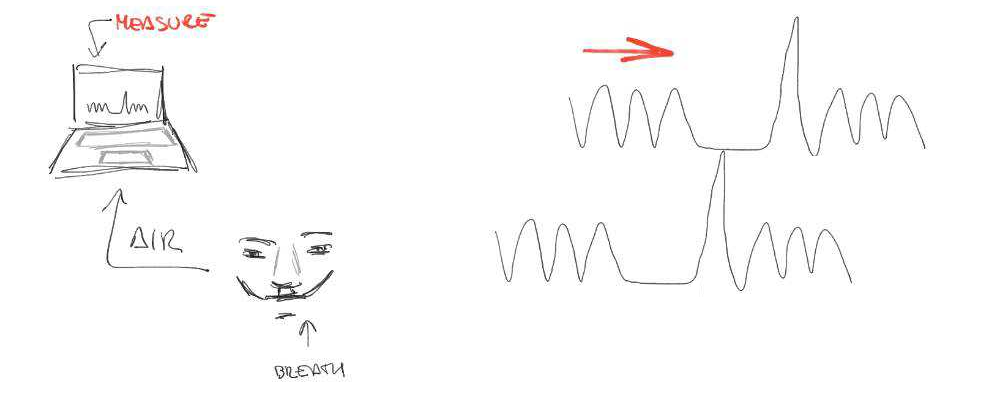

Quick recall: BOLD effect

Cerebrovascular Reactivity

Cerebrovascular Reactivity (CVR) is the response of cerebral vessels to a vasoactive stimulus (e.g. CO2) to provide sufficient O2 to cerebral tissues¹

CVR can be measured during BOLD fMRI experiments with Breath-holds (BH), that induce the subject into a state of hypercapnia²

The vessels dilate → Increase of blood flow → Increase of %BOLD signal

CVR mapping [%BOLD/mmHg] can be obtained through a linear regression analysis using the recordings of exhaled CO2 (reliable proxy of CO2 partial pressure in arterial blood)

CVR is a vascular response

to CO2 changes that can be estimated with respiratory tasks and BOLD imaging.